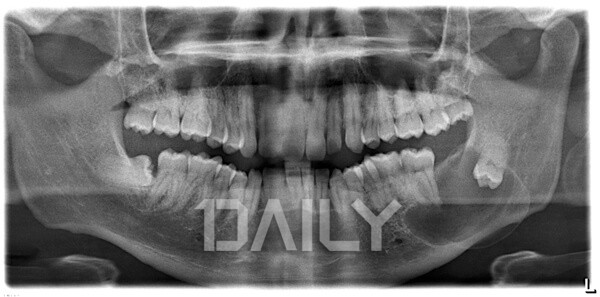

»ç¶û´Ï´Â ¸¶Ä¡ ù»ç¶ûÀ» ¾ÎµíÀÌ ¾ÆÇÁ´Ù°í ÇÏ¿© ºÙ¿©Áø ¸íĪÀ¸·Î, ¸íĪ ÀÚü¸¸ ³õ°í º¸¸é ¾Æ¸§´äÁö¸¸ ½ÇÁ¦·Î´Â »ç¶û´Ï ¶§¹®¿¡ °íÅëÀ» ¹Þ´Â »ç¶÷µéÀÌ ¸¹´Ù. »ç¶û´Ï´Â Å« ¾î±Ý´Ï Áß ¼¼ ¹øÂ° À§Ä¡ÀÎ Á¦3´ë±¸Ä¡¸¦ ¸»Çϴµ¥, ±¸° ³»¿¡ °¡Àå ´Ê°Ô ³ª¿À´Â Ä¡¾Æ´Ù.

¾à 7%ÀÇ »ç¶÷¿¡°Ô´Â »ç¶û´Ï°¡ ¾Æ¿¹ ¾ø±âµµ Çϸç, ÀԾȿ¡ °¡Áö°í Àְųª ³ª¿À´Â °³¼ö´Â 1°³ºÎÅÍ 4°³±îÁö »ç¶÷¸¶´Ù ´Ù¸£´Ù. »ç¶û´Ï°¡ Á¤»óÀûÀ¸·Î ³ª¿Í û°áÇÏ°Ô À¯Áö °ü¸®°¡ µÇ¸é ¾Æ¹« ¹®Á¦°¡ µÇÁö ¾ÊÁö¸¸ ´ëºÎºÐ Ä¡¿ ¸Ç ¾ÈÂÊ ³¡¿¡¼ °ø°£ÀÌ ºÎÁ·ÇÑ »óÅ·ΠÀÚ¸®¸¦ Àâ°í ÀÖ´Â °æ¿ì°¡ ¸¹¾Æ ¹®Á¦°¡ µÈ´Ù. ±×·¸´Ù¸é Á¤È®È÷ ¾î¶² ¹®Á¦¸¦ ¾ß±âÇÏ´ÂÁö, »ç¶û´Ï¸¦ ¿Ö »Ì¾Æ¾ß ÇÏ´Â °ÍÀÎÁö ¾Ë¾Æº¸ÀÚ.